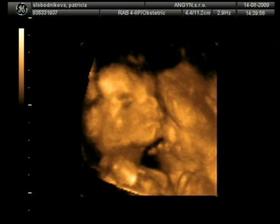

Termín pôrodu vychádza na 24.12.2009 - takže bude vianočný darček 🙂)) 6.7.odber krvi na AFP testy, 15.7.su vysledky a vsetko je ok 🙂) 14.8. 4D ultrazvuk - máme 413g (22tt) a vyzerá to na dievčatko 🙂)) TP podla velkosti: 23.12. 13.10. - utz v 30tt, resp.takmer v 31tt..máme 1700g..podľa veľkosti 31+2tt a všetko ok 🙂)